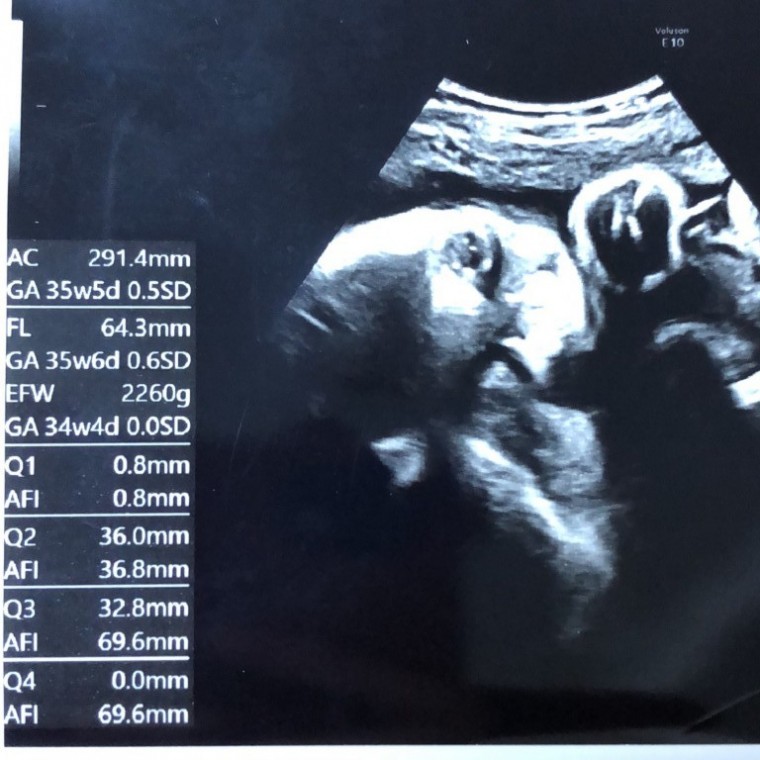

妊娠9ヶ月の超音波写真

恥ずかしがり屋さん

なかなかお顔を見せてくれなかったけどやっとこ少し。 お肉がついて赤ちゃんらしくなってきている。

妊娠9ヶ月(35週1日)撮影日:2018年9月28日